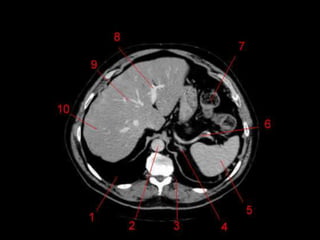

• TC: Tres fases

– Arterial (10 a 20 segundos)

– Fase venosa portal ( 30 segundos )

– Fase venosa hepática (60 segundos)

Técnicas de Imagem •US: Primeiro exame pedido ao: 1) dor no hipocondrio direito; 2) testes de função hepáticas anormais; 3) suspeita de malignidade. • TC: Tres fases – Arterial (10 a 20 segundos) – Fase venosa portal ( 30 segundos ) – Fase venosa hepática (60 segundos) • TC Portografia: Metastases.